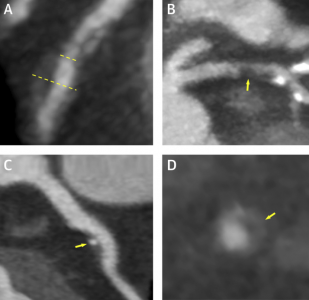

Έτσι η ιστορία της αξονικής στεφανιογραφίας, που ξεκίνησε από την περιγραφή του αυλού και την ανατομία, εξελίχθηκε στον χαρακτηρισμό της αθηρωματικής πλάκας και τη γνώση των χαρακτηριστικών της υψηλού κινδύνου πλάκας. Γνωρίζουμε επίσης ότι μπορούμε να επέμβουμε φαρμακευτικά, με τη μεγαλύτερη αξία να έχουν οι στατίνες, που αποτελούν φάρμακα αντιλιπιδαιμικής αγωγής, αυξάνοντας την επασβέστωση του νεκρωτικού πυρήνα της αθηρωματικής πλάκας και καθιστώντας την πιο σταθερή. Ήδη το 2007 ο Μotoyama περιέγραψε τα χαρακτηριστικά της υψηλού κινδύνου αθηρωματικής πλάκας, της πλάκας που, ανεξαρτήτως του βαθμού στένωσης, μπορεί να προκαλέσει οξέα συμβάματα, όπως οξύ έμφραγμα και καρδιακό θάνατο. (4)

Παράδειγμα μη αποφρακτικής αθηρωματικής πλάκας υψηλού κινδύνου